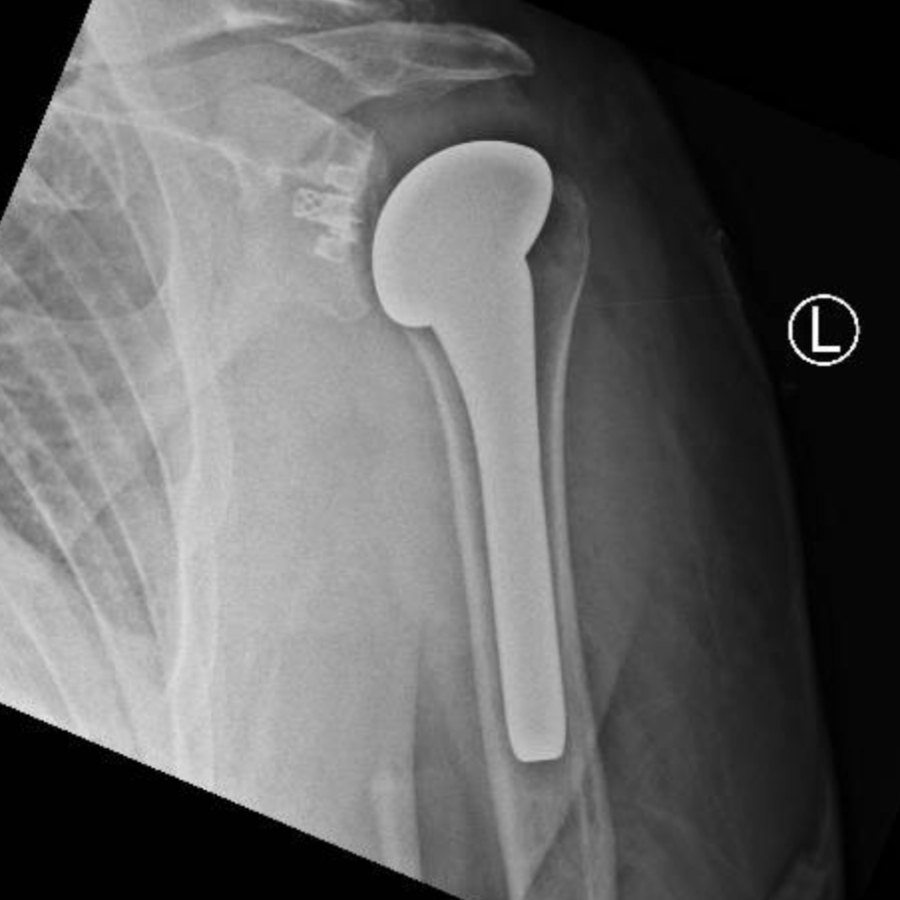

Surgery is considered when other treatments are no longer effective in controlling your symptoms. Shoulder joint replacement is a very effective treatment for shoulder arthritis. The operation removes the arthritic joint surfaces and replaces them with a combination of metal and plastic surfaces. This operation is extremely successful in controlling pain and improving function of the shoulder and the whole arm. If you are being treated for shoulder arthritis and would like to find out more about shoulder replacements, or if your current treatments are not working, please book an appointment at The Cheshire Shoulder and Elbow Clinic.